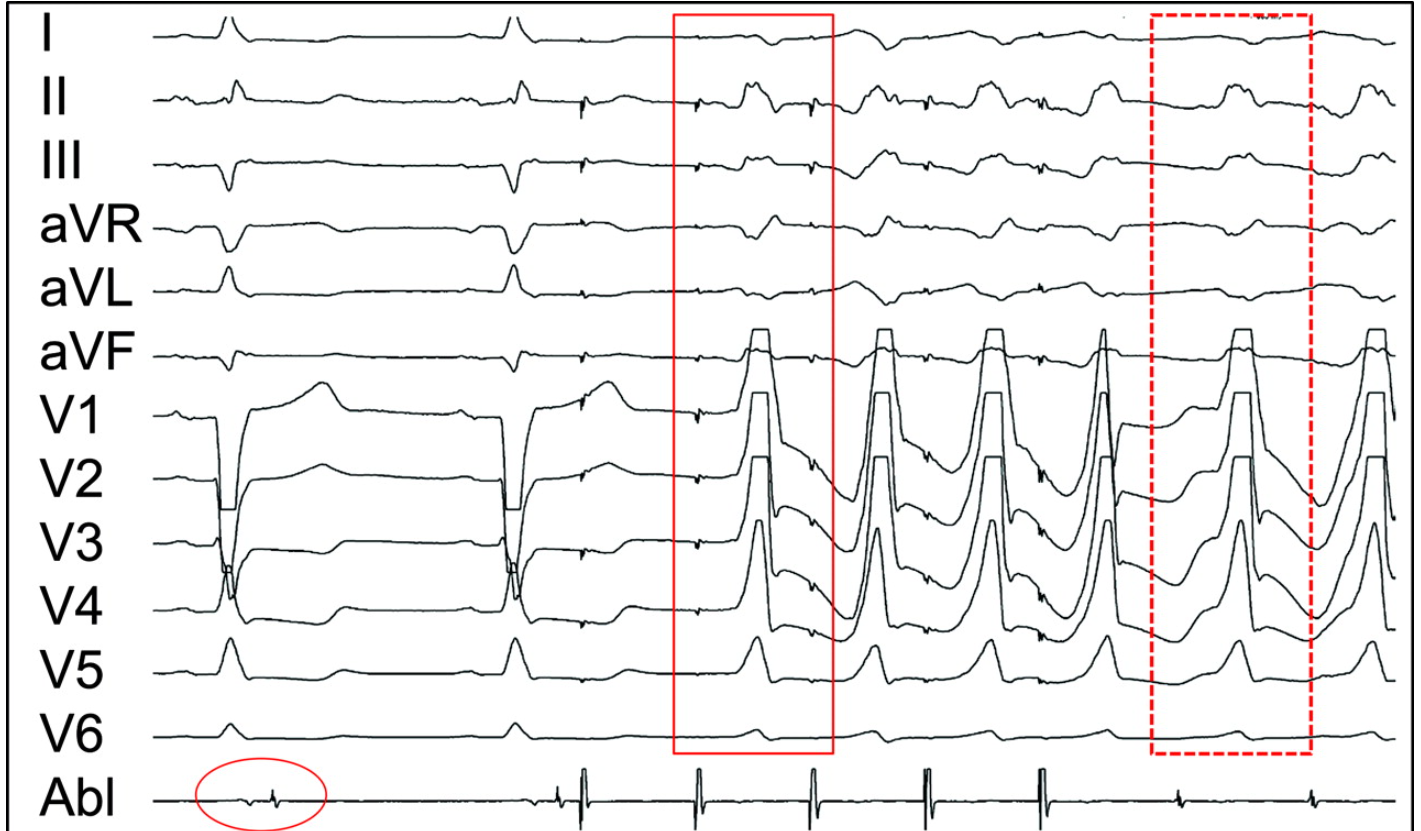

Illustrative case

vt_pacemap.jpg